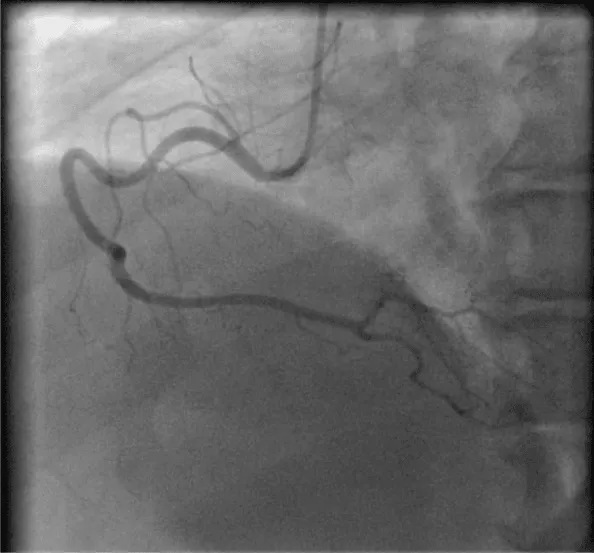

Her initial vital signs upon presentation to the hospital were; blood pressure: 161/76 mm Hg, heart rate: 96 beats per minute, respiratory rate: 27 breaths per minute. Physical exam revealed a cardiac auscultation findings of a grade 2 diastolic murmur which was loudest at the 2nd right intercostal space as well as a grade 2 systolic flow murmur. Cardiac biomarkers were elevated with initial troponin-I of 0.33 ng/mL, peak of 2.28 ng/mL and subsequent down trend. Electrocardiography (Figure 1) showed sinus rhythm with anterior and inferolateral T wave inversion and chest radiograph (Figure 2) was unremarkable. She underwent coronary angiography which revealed normal coronary arteries. The takeoff of the right coronary artery (RCA) was noted to be superior and anterior to its normal position (Figures 3A and 3B). Transthoracic and transesophageal echocardiography (TEE) revealed normal left ventricular systolic function and severe insufficiency of the aortic valve with Quadricuspid morphology (Figure 4A in Diastole, Figure 4B in Systole, Figure 4C Long Axis of the aortic valve). She underwent aortic valve replacement with a # 19mm ON-X mechanical valve. Intraoperatively it was noted that the ostium of the right coronary artery was over the aberrant leaflet. Her postoperative course was complicated by the development of supraventricular tachycardia, posteriorly localized pericardial effusion, severe hemolytic anemia, renal failure and pancreatitis leading to her death eleven days after the surgery.

Figure 3a: Left anterior oblique View of the RCA.

Figure 3b: Right anterior oblique view of the RCA.

In our case as we described, the QAV was noted to have three equal sized cusps and one larger cusp and is a type E valve according to the 1973 Hurwitz and Roberts’s classification [4]. Congenital QAV predisposed her to the development of severe AI and was associated with the finding of an anomalous origin of the right coronary artery. The RCA originated from the right dorsal or posterior cusp of the aortic valve and the left main coronary artery originated from the left ventral or anterior cusp, nomenclature of the cusp orientation is as proposed by Fernandez et al. [13]. In their study of quadricuspid aortic valves in Syrian hamsters [13]. The supernumerary cusp was identified as the right dorsal cusp and the RCA originated from that corresponding right dorsal sinus which was identified intraoperatively. Although the presence of the patient’s comorbidities such as uncontrolled HTN, obesity and recurrent pancreatitis did not have a causal relationship with the finding of QAV or the development of severe AI, they likely played a role in her post-surgical mortality.